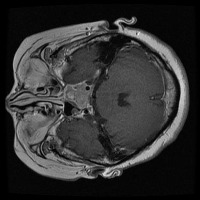

tumor otak Computer Vision Project

Here are a few use cases for this project:

Medical Diagnostics: This model can be used for assisting healthcare professionals in diagnosing brain tumors by classifying them into glioma, pituitary, or meningioma, which can save time and lead to early and accurate disease diagnosis.

Health Monitoring Software: It can be implemented in health and wellness apps to monitor a patient's MRI scans regularly, thus providing an early warning system for possible tumor growth.

Training medical students and resident doctors: The model can be used as a training tool for medical students and resident doctors to better understand and identify different types of brain tumors from MRI images.

Research Studies: It may be used by scientists and researchers for creating more focused and comprehensive studies on brain tumors, contributing to advancements in the respective field of study.

Telemedicine: This model can be helpful in telemedicine portals where expert opinion may be lacking. The model could provide initial diagnosis based on MRI scans before a patient consults with a healthcare professional.